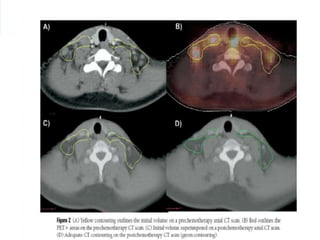

 The contouring process is as follows:

 1. The CT images of the pre chemotherapy PET/CT are used to

 2. The PET images of the pre chemotherapy PET/CT are used

PET as determined by FDG uptake

 3. The pre chemotherapy PET/CT is fused with the post

are imported to the planning CT images

 4. The post chemotherapy tissue volume, which contained the

other anatomic changes.

 The CTV

normal structures